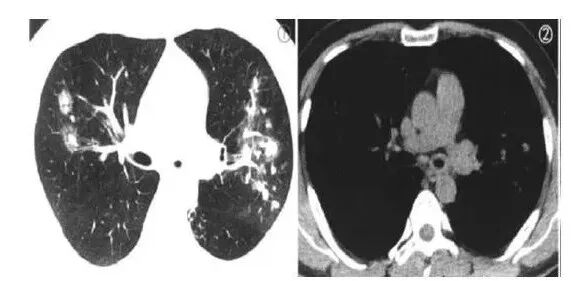

气道壁增厚,咳喘加重,左肺实变,感染,曲霉,鉴别结核。

老年男性,病史20天,三个月前肺CT左斜裂略增厚。现左肺容积缩小,左下背段实变影。先排除异物,吸入性病变后,考虑感染性病变。

老年人,气管,支气管壁明显均匀增厚,复查左肺下叶可见实变,考虑炎性病变,结核,不排除合并淀粉样变性

左肺上叶沿支气管条形密度,左叶间胸膜局部增厚。三个月复查左肺体积变小,肺门旁团状实变,左侧胸腔积液。首诊倾向感染性病变,结核?鉴别肿瘤,鳞癌,小细胞癌。

老年男性,咳嗽胸闷,三月前左肺叶间胸膜增厚,咳嗽胸闷加重,三月后左肺容积变小,左侧支气管管壁增厚,左肺实变,首先考虑为炎性病变

老年男性,肺气肿,3月前左主支气管管壁增厚,左侧斜裂增厚,3月后复查左主支气管阻塞,左肺实变不张,胸廓缩小,纵膈左移,小叶间隔结节样增厚,考虑恶性,鳞癌可能大,鉴别结核

左侧支气管壁增厚,管腔狭窄,三月后复查,左侧支气管狭窄程度加重,但管腔形态存在,远端伴阻塞性改变,病变并累及到右侧支气管壁,慢性过程,考虑炎性可能性,结核首选

左主支气管壁增厚,管腔变窄,斜裂增厚,3个月后,左肺大片实变影,密度不均,气管堵塞,左侧胸腔变小,纵隔左移,首先考虑支气管炎性改变,结核,鉴别鳞癌。

老年男性,左肺主支气管管壁轻度环形增厚,三个月复查后明显增厚,管腔变窄,支气管闭塞,左侧胸廓塌陷,纵隔左侧移位,左肺见大片状实变密度影,考虑结核可能大,鉴别鳞癌